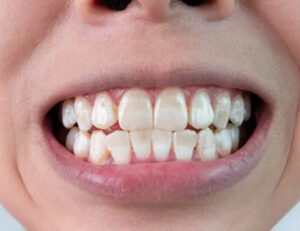

着色汚れ

着色汚れは、最初は歯の表面に付着するだけですが、時間が経つと歯に浸透して表面におうとつを作り、ザラザラとした感触の原因になります。

主な原因は、コーヒーや紅茶、赤ワインなどに含まれるタンニンやポリフェノール、カレーやソース、ベリー系の果物など色の濃い食品です。

さらに喫煙習慣がある場合、タバコのニコチンやタールが歯に強く付着します。

これらの物質は粘着性が高く、通常の歯磨きだけでは取り除きにくく、長期間蓄積すると歯の表面を覆う厚い膜となり、ザラザラ感を引き起こします。